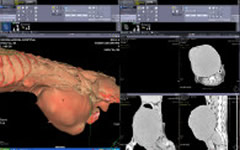

術前CT

術前CTから、巨大な腫瘍によってお腹の内臓は正常な位置にありません。